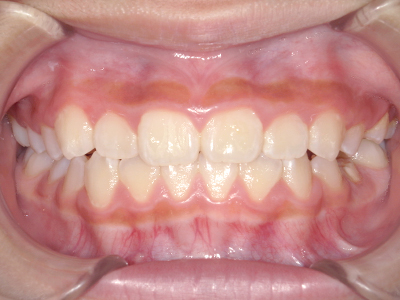

歯並びやかみ合わせを正しく整えると、笑顔や発音の自信につながり、むし歯・歯周病・口臭の予防にも役立ちます。

歯並びの相談に来られるお子様は、口呼吸をしているケースが多く、これが歯並びに大きな影響を与えています。

↓ - さまざまな不正咬合が生じる

ないき歯科クリニックでは、上あごの成長不足を補い、鼻呼吸を獲得しつつ歯列を整え、将来のお口をより健康な状態にすることをゴールに定める矯正治療をおこなっています。